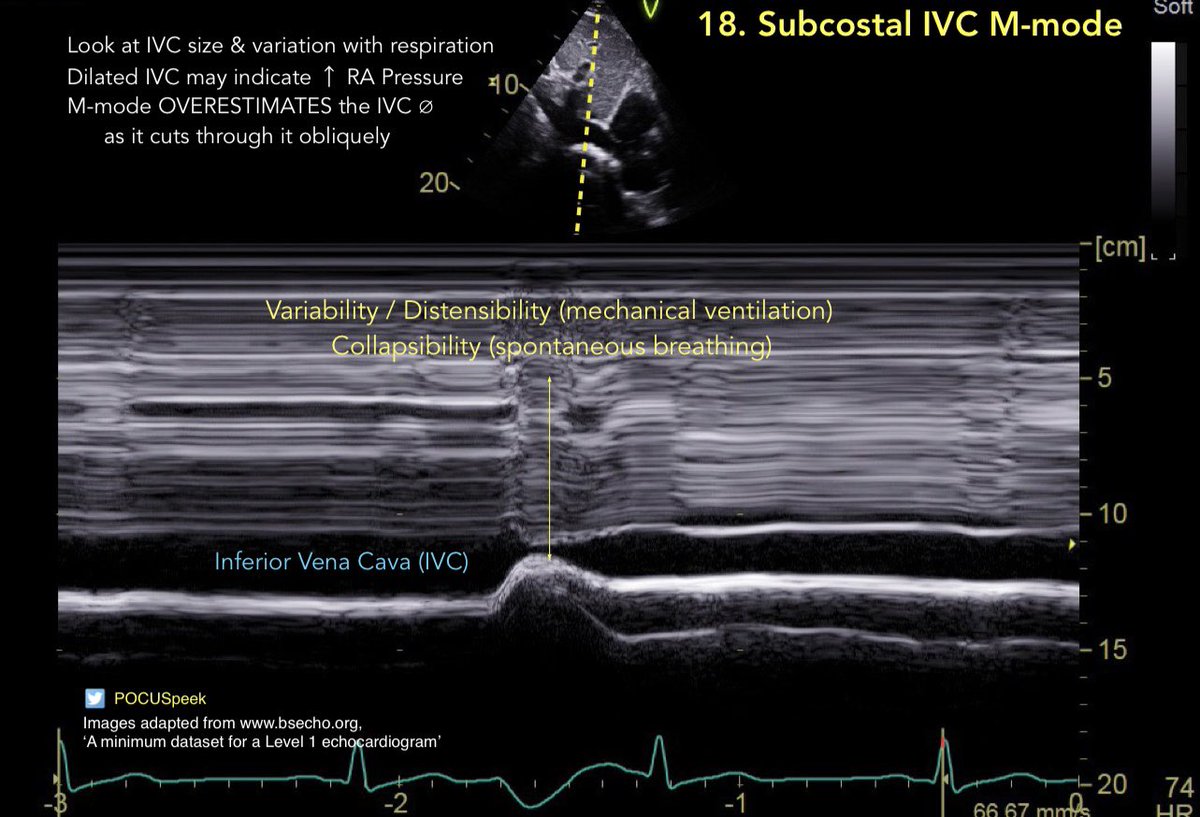

Some annotated #firstecho #POCUS main views 👇🏻 3/3

POCUSpeek's tweet image. Some annotated #firstecho #POCUS main views 👇🏻 3/3